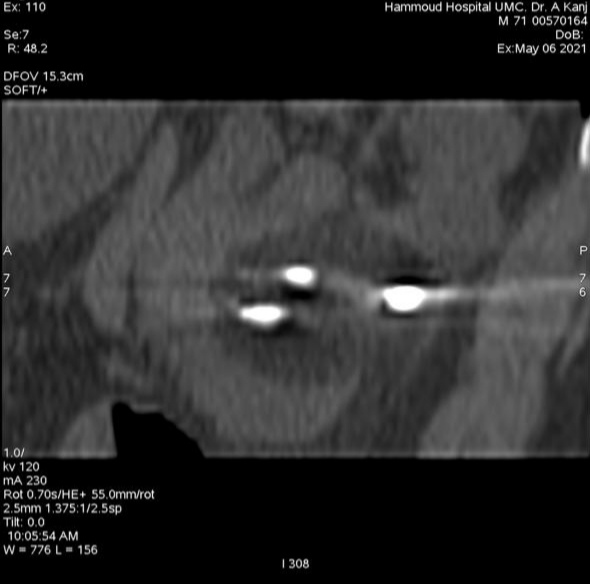

طبي جديد في مستشفى حمود الجامعي لأول مرة في الجنوب، عبارة عن علاج ورم ضخم في

الكلية مكون من كتلة سرطانية تتخطى ال٦ سنتم بالتقنية الحديثة Cryoablation Of Tumor

Under CT

وهي

تقنية تجميد وقتل الأورام السرطانية الخبيثة دون إجراء عملية جراحية ودون آلام.